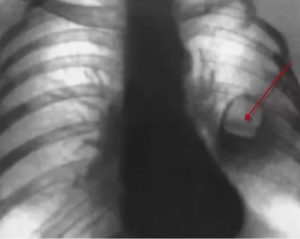

Также следует отметить тот факт, что при формировании каверны очень важно определить её тип – гнойная или раковая.

Подобные действия можно осуществить, обратив внимание на следующие признаки:

- если в кольцевидной тени отсутствуют завершённые контуры, то это символизирует о наличии периферического рака;

- в случае развития раковой каверны её полость и стенки толстые и бугристые, внешние границы лучистые;

- при развитии гнойной каверны наблюдается чёткое выделение уровня жидкости и наличие перифокальных очагов.

Обратив внимание на эти моменты, не составит никакого труда найти различия между раковой и гнойной каверной на рентгеновском снимке.

В отличие от абсцесса, туберкулезные инфильтраты сопровождаются менее выраженной клинической картиной, отсутствием гнилостного запаха у мокроты. Важные рентгенологические признаки, указывающие на инфицирование МБТ – отсутствие горизонтального уровня жидкости и свежие очаги отсева неподалеку от инфильтрата.

Кроме того, возможно обнаружение в анализе мокроты палочки Коха – возбудителя специфической инфекции.

Рентгенологически раковая опухоль определяется как бесформенное бугристое затемнение с просветлением в центре. Микроскопия мокроты или бронхиальных смывов позволяет обнаружить в биоматериале атипичные клетки.

Раковая опухоль на рентгене имеет нечеткие края